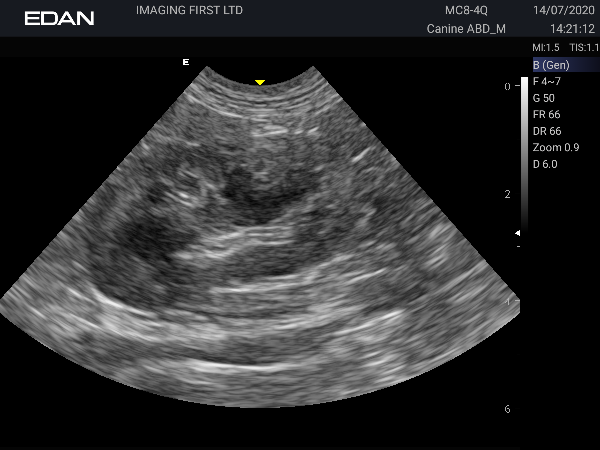

Images from the Acclarix AX3 Vet

This machine produces beautiful images. The Edan Acclarix AX3 travelled with me on a couple of visits to practices. I used the linear probe on cat abdomen and the microconvex on a Bernese Mountain Dog and was able to see the duodenal papilla in both. As well as scanning my own dog Pippi, I scanned a cat and dog heart – it generally performed well and the linear phased probe gave superb images for the price.

In summary this machine has been a lot of fun to review. The image quality particularly on the linear probe in cats is superb, and I’ve enjoyed seeing details on an abdominal scan I wouldn’t normally get to see. The niggles I’ve named are nit-picking – if these are not a big deal to you do not let them put you off this great little machine.